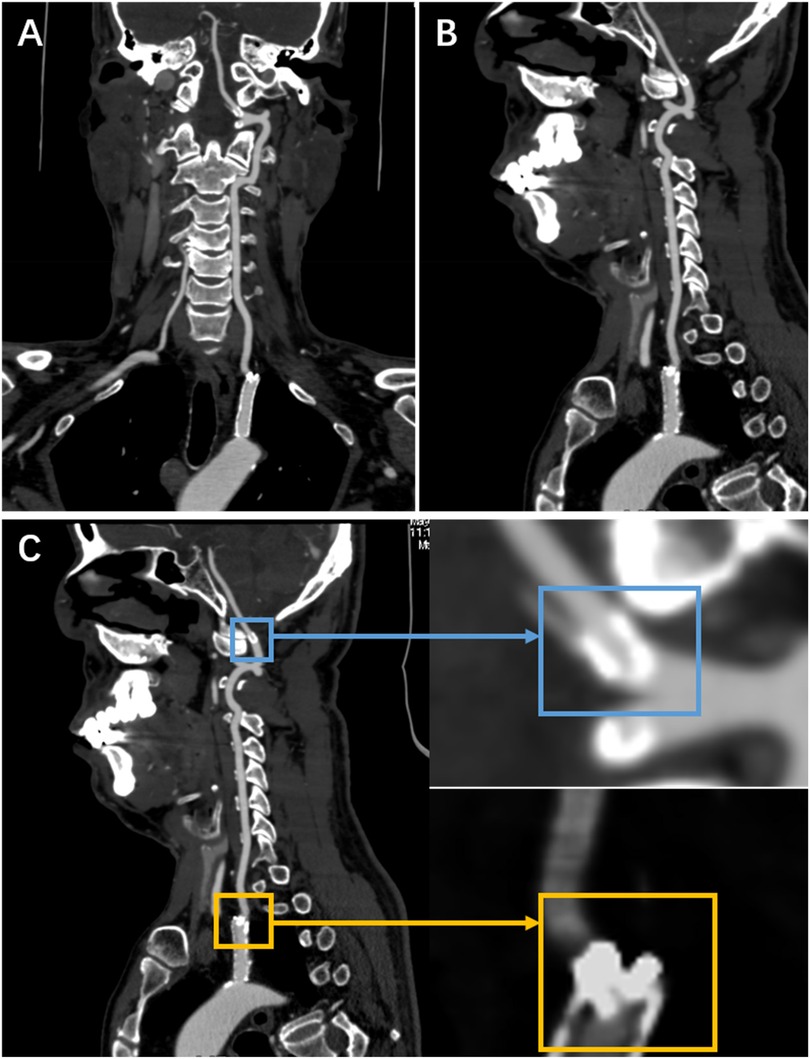

Surveillance CTA performed one year following the VA stenting revealed the mid-stent fracture with distal fragment migration to the V3 segment, and both stent debris remained patent with no pseudoaneurysm (Figure 2). Then, we strongly recommend the patient undergo DSA to assess the vascular condition accurately. However, he was asymptomatic and was experiencing psychological distress from multiple previous neurointerventional procedures, so he declined to undergo the DSA examination. Finally, respecting patient autonomy, after the detailed discussion, we opted for maintaining antiplatelet therapy, Aspirin (100 mg/d), with close observation. To date, he is without symptoms. Figure 3 shows the timeline of the complete illness course of this patient.

CT scan images showing different views of the cervical spine and surrounding areas. Panel A displays a coronal view, while panels B and C present sagittal views. In panel C, two magnified insets are highlighted with blue and yellow boxes, indicating specific areas of interest.

Figure 2. The CTA was done a year following stenting of the left VA origin. (A,B) They show a stent fracture in the centre, with the distal fragment migrating to the V3 segment. (C) It shows a local magnification of both fragments (the yellow rectangle indicates the proximal fragment, the blue rectangle represents the distal fragment).